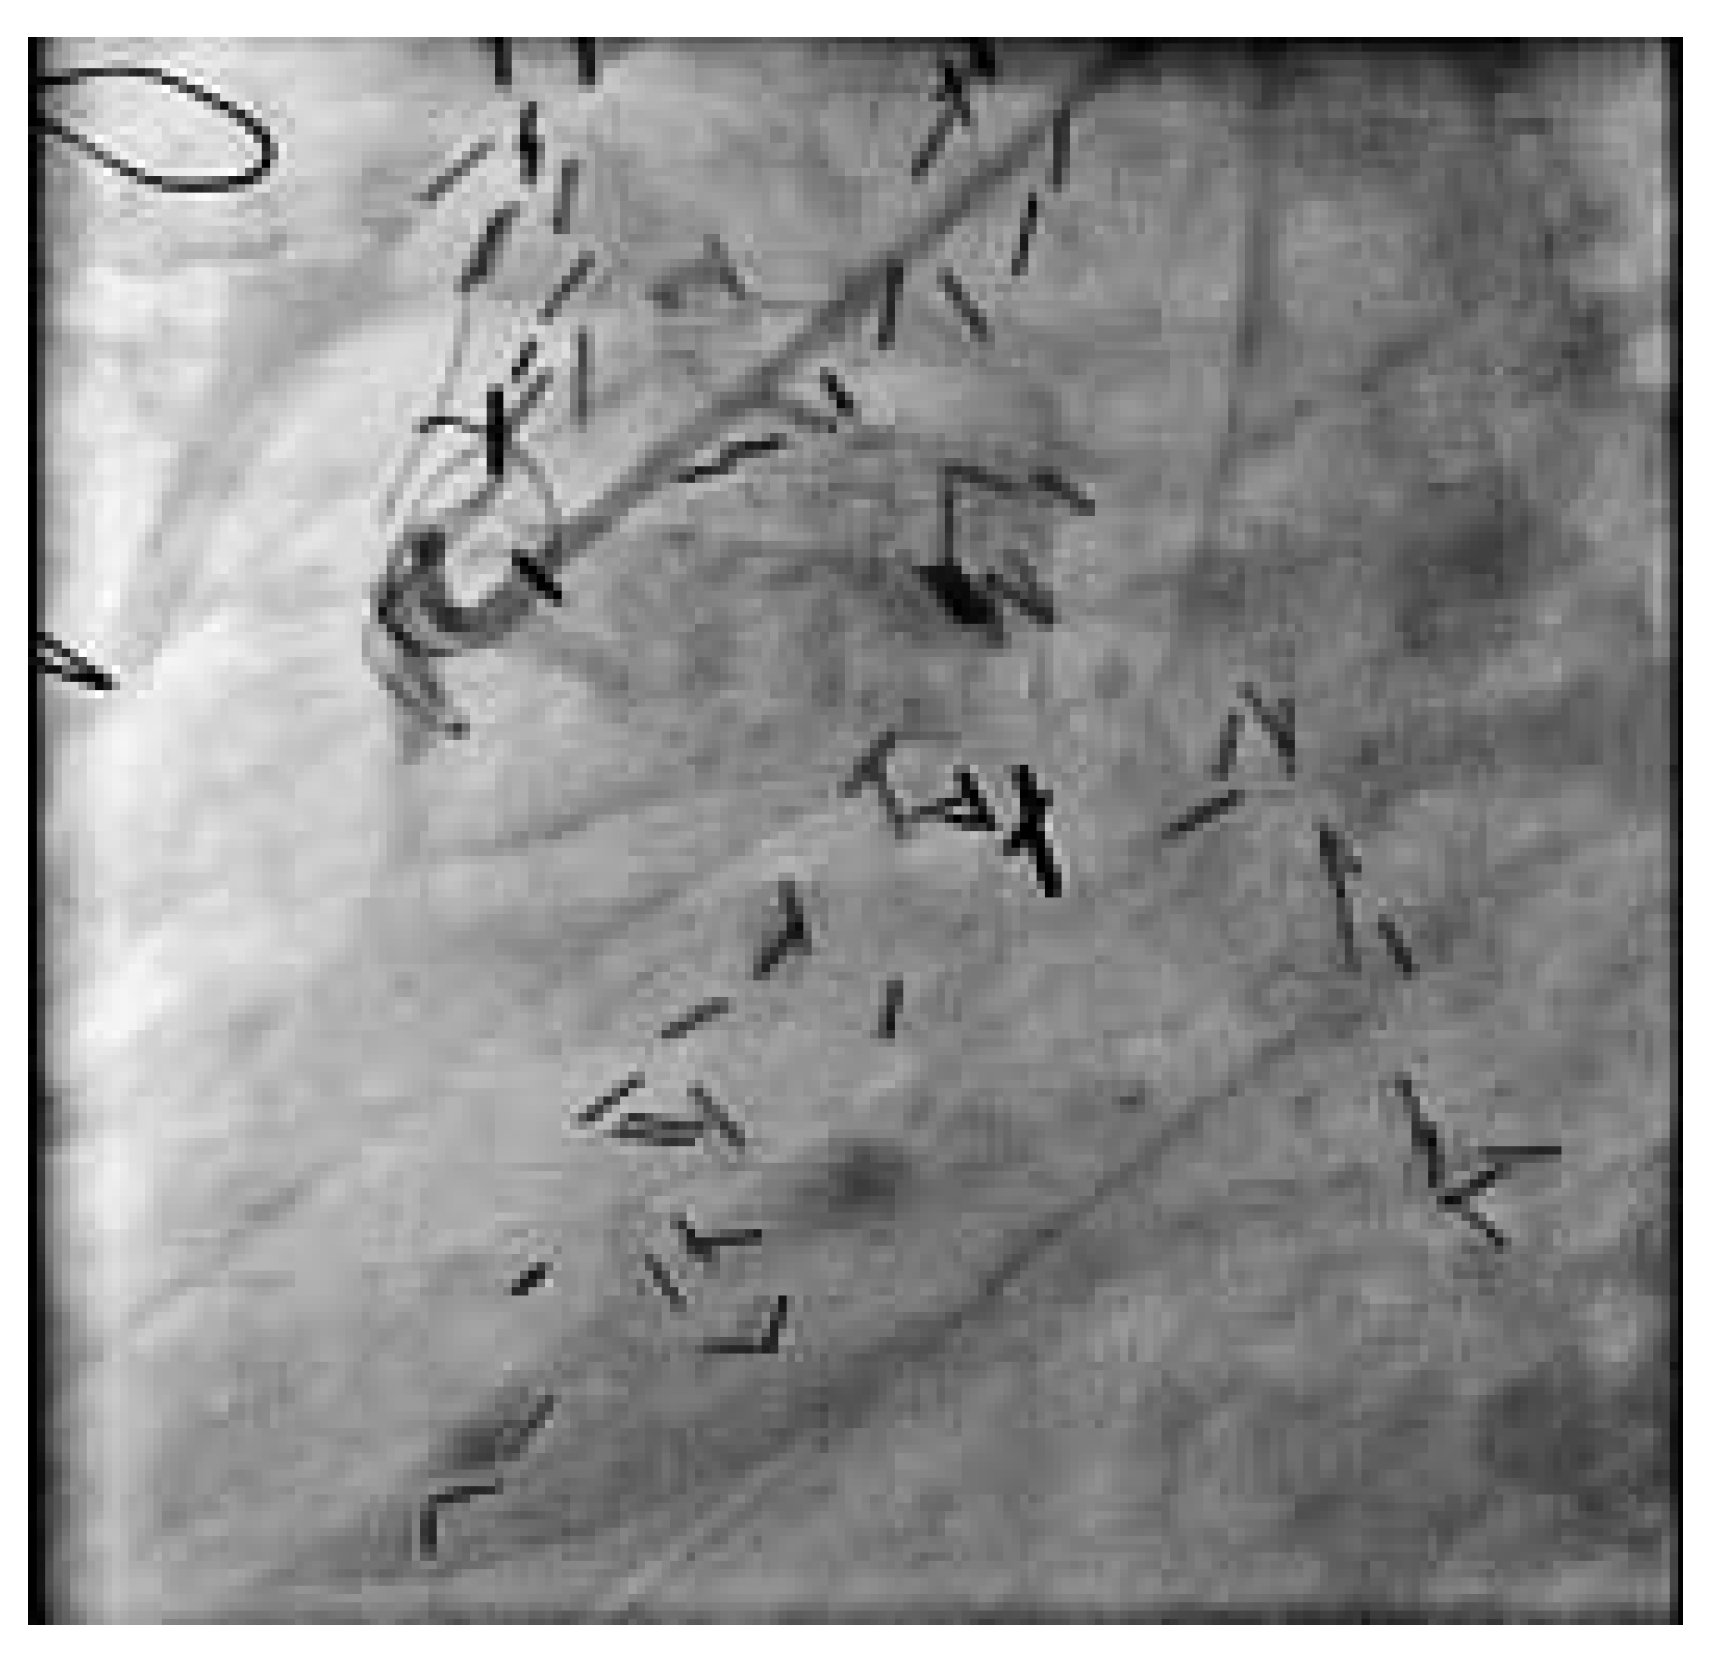

Abbildung 6. Nach Drahtpassage und trotz mehrfacher, langstrekkiger Ballon-Dilatation und intravaskulärer Nitrat-Gabe kommt kein antegrader Fuss im Venengraft zustande.

Beim zweiten Patienten handelt es sich um einen 72jährigen Patienten, welcher sich 1980 erstmals einer Bypass-Operation unterzog. 1988 wurde er reoperiert (LIMA zu RIVAund Diagonal-Ast, RIMA auf PLA des Ramus circumflexus, Vene zum RIVP der RCA und zum 2. PLA). Nach einer Prostata-Radikaloperation im Sommer 2003 kam es zu einer progredienten Angina pectoris CCS III. Trotz voll ausgebauter antiischämischer Behandlung traten immer häufigere Episoden von Ruhe-Angor auf. Im Februar 2004 zeigte die Koronarangiographie einwandfreie arterielle Bypass-Verhältnisse und einen proximalen, langstrekkigen Verschluss des Venengraftes (Abb. 5). Nach Drahtpassage und mehrfacher, langstreckiger Ballondilatation und intravaskulärer Nitrat-Gabe kommt kein antegrader Fuss zustande (Abb. 6). Erst nach mehreren Passagen mit dem Thrombusaspirationskatheter kommt der Venenbypass und die angeschlossenen Gefässe zur Darstellung. Das Endresultat nach Stenteinlage (Abb. 7 und 8) ist sehr zufriedenstellend. Der Patient ist seit dem Eingriff beschwerdefrei.